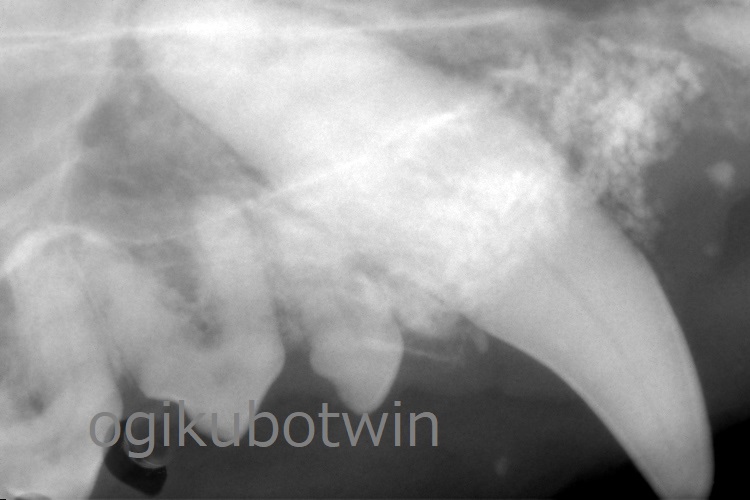

両側下顎の第一後臼歯(奥歯)は近心、遠心ともに歯周病が進行していいたため、温存するためにその両側の第四前臼歯(奥歯)と第二後臼歯(奥歯)を抜歯しました。

両側の上顎犬歯は歯周ポケットが深くなっていましたが、鼻腔まで到達していないことが確認できたので再生治療を行いました。

両側の犬歯ともに軟組織を除去して、骨を露出させた状態でエムドゲインとβ-TCP(骨補填剤)を用いて充填させました。

9か月後に鎮静下にてレントゲンを撮影し、再生治療の経過を確認します。

9か月後の検診時、犬歯の歯周ポケットは浅くなっており、経過良好です。